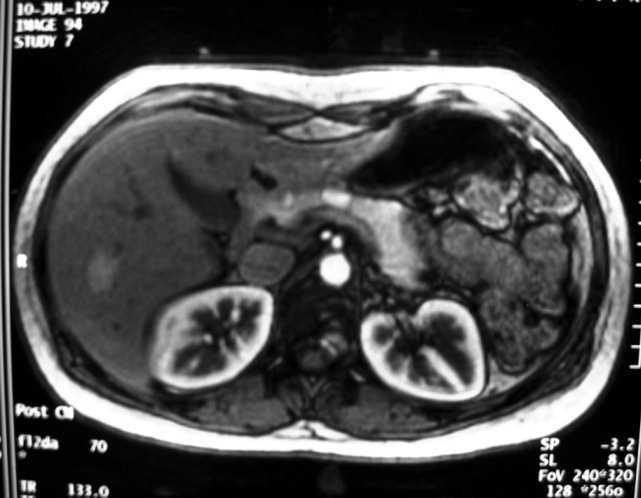

Figura 1. Adenoma hepático en relación con la toma de anticonceptivos orales.

Caso clínico. Mujer de 30 años con el único antecedente personal de una meningitis linfocitaria en la infancia sin secuelas. No seguía ningún tratamiento habitual en la actualidad. Se inició tratamiento con anticonceptivos orales a petición de la paciente a la edad de 21 años. Acudió 2 años después a urgencias del hospital por dolor tipificado como cólico biliar. En el estudio ambulatorio de dicho cuadro se realizó una ecografía abdominal, en la que se observó una lesión nodular en segmento 5 del lóbulo hepático derecho. La resonancia magnética (RM) hepática reveló una lesión sugestiva de adenoma hepático en el segmento 5 de unos 24 mm de tamaño (fig. 1). El estudio fue completado con una punción-aspiración con aguja fina (PAAF) de la lesión, cuyas extensiones citológicas resultaron negativas para malignidad. Se suspendieron los anticonceptivos orales después de 3 años de su inicio. Posteriormente, en consultas sucesivas, la lesión hepática había desaparecido en las pruebas de imagen. En la actualidad la paciente se encuentra asintomática y no toma anticonceptivos orales.